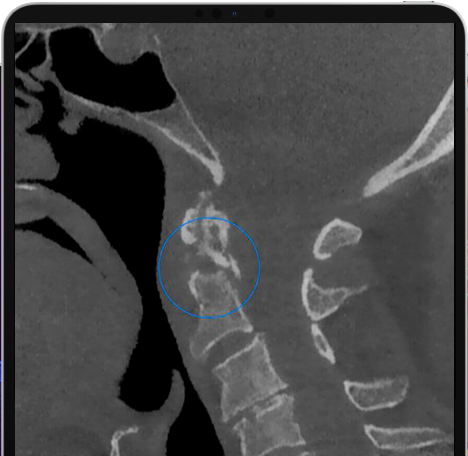

Veja exemplos de diagnósticos de imagem

- O gerador com ânodo giratório e ponto focal de 0,3 mm permite obter imagens de altíssima definição para ver detalhes e microestruturas que não podem ser investigados com dispositivos tecnológicos padrão;

- Algoritmos de reconstrução e processamento de imagem, resultado dos vinte anos de experiência da NewTom, permitem obter rapidamente imagens 2D e 3D excepcionais.